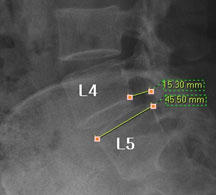

모커리한방병원 위 뼈가 50%정도 밀려나간 모습 이미지

척추전방전위증은 척추 주변, 특히 척추 후방에 있는 후관절 주변의 근육과 인대 그리고 후관절 자체가 퇴행되어 척추 뼈를 제대로 붙잡아 주지 못해 위아래 척추 뼈가 앞뒤로 밀려 나가면서 발생하는 척추질환을 말합니다.